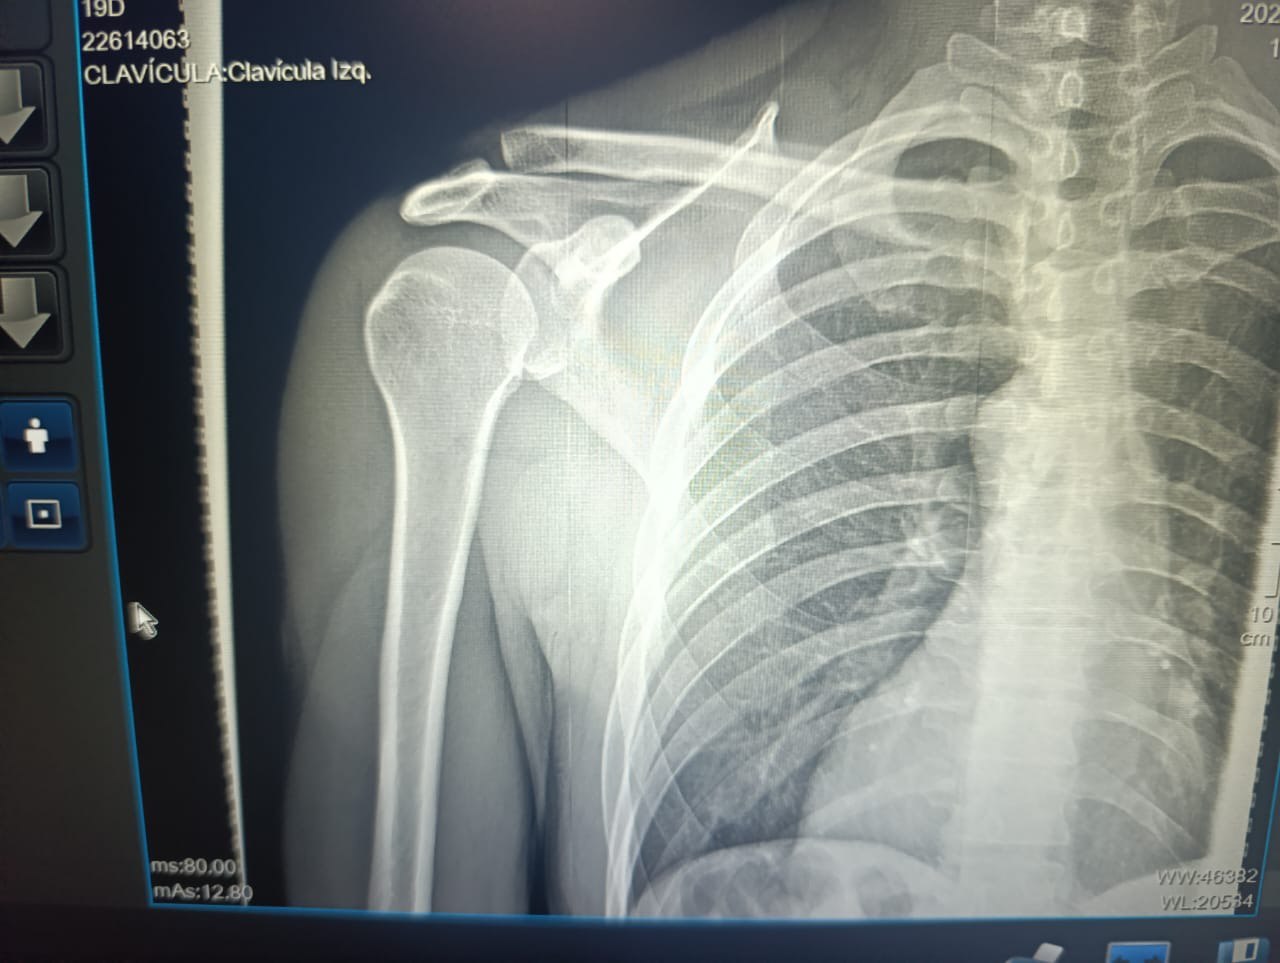

«Hoy acudí al servicio de rayos x para hacer seguimiento a una operación que me

hicieron y fui atendido de manera inmediata y gratuita, una imagen excelente.», mencionó Jackson Medina, paciente con seguimiento por lesión en la clavicula.